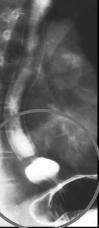

Hernie

hiatale de Type I .Le cardia et une partie marquee

de estoma glissent a sus diapragmatique |

Image du type I en

TOGD ++ double de contrast |